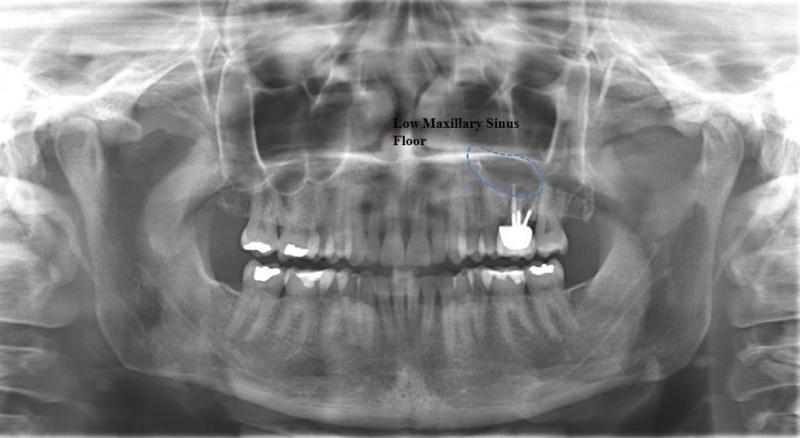

Surgery to insert osseo-integrated dental implants and Maxillofacial implants for attaching craniofacial prostheses (See Images Below)

Dento-alveolar surgery (impacted teeth like wisdom teeth and canines, difficult tooth extractions, extractions on medically compromised patients, apicoectomy, bone grafting/bone harvesting or pre-prosthetic surgery) (See Images Below)